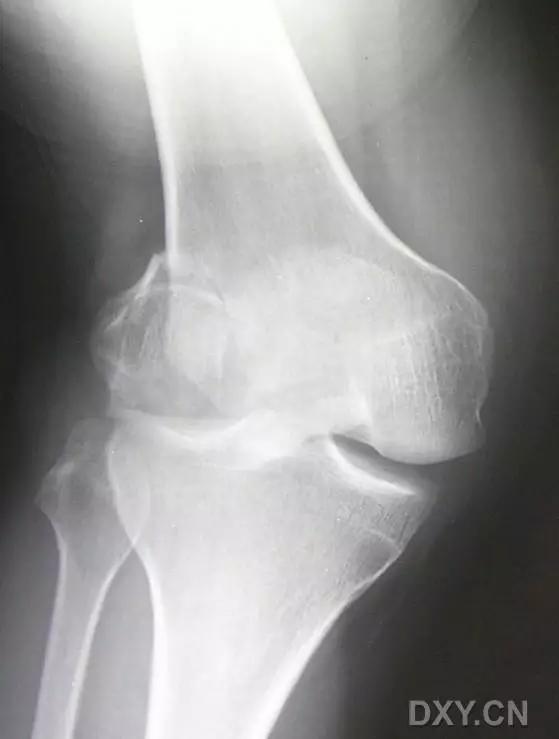

11. Bumper 骨折 (保险杆骨折)

是汽车保险杠撞击膝关节外侧,导致的胫骨平台粉碎性骨折,伴有软骨面挫裂和腓骨头骨折。初诊,X 线上正侧位很容易轻忽平台的粉碎性,CT 平扫及重建可明确伤情,MRI 可了解副韧带及叉韧带情况。